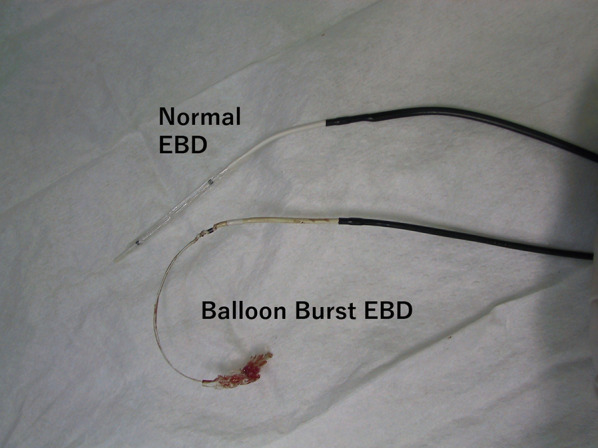

A 30-year-old woman was transported to our hospital by ambulance due to epigastric pain. A laboratory analysis revealed the following: white blood cells, 4000/mm3; total bilirubin, 3.0 mg/dL; alkaline phosphatase, 640 IU/L; GOT, 395 IU/L; GPT, 746 IU/L; and amylase, 37 IU/L. Abdominal CT demonstrated multiple gallbladder (GB) stones without inflammation of the GB; the diameter of the common bile duct (CBD) was 10 mm. ERCP was performed under the suspicion of CBD stones. Bile duct cannulation was easily performed. Cholangiography revealed no apparent CBD stones. Although EBD is not routinely carried out in this situation, we carefully performed EBD due to the suspicion of CBD stones, and carefully taking the clinical course into consideration. Before the procedure, a dilatation balloon (Hurricane RX Rapid Exchange, Boston Scientific, MA, USA) was inflated as a precaution in order to check the condition of the balloon. The dilatation balloon was then passed over the guidewire and located at the site of the biliary sphincter. The balloon was inflated to 2 atmospheres of pressure. After the procedure, the balloon suddenly burst. We were unable to remove the EBD catheter because the balloon was caught at the biliary sphincter (Figs. 1, 2). A computed tomography (CT) scan showing the burst balloon located at the site of the biliary sphincter (Fig. 3). Finally, we had to perform surgical intervention to remove the EBD. We made an incision at the pylorus, and then we manually pulled the EBD catheter through this incision, as shown in Fig. 4a, b. The broken catheter was successfully removed without injuring the biliary sphincter. Cholecystectomy, CBD exploration, and then removal of the CBD stone were performed. A T-tube was inserted for drainage. Intra-operative cholangiography revealed no residual stones and no biliary sphincter abnormality (Fig. 5). The burst balloon of the EBD catheter is shown in Fig. 6. The patient was discharged without any complications after removal of the T-tube on post-operative day 14.

EBD is the treatment of choice for patients with CBD stones. The high success rate and safety of this modality have been well established by a number of studies [ref. 1–ref. 3]. Complications of EBD, such as pancreatitis, hemorrhage, perforation, and infection have been reported [ref. 4–ref. 9]. In the current case, we demonstrated balloon burst of an EBD catheter as a rare complication of EBD. According to the product information of the EBD catheter, the balloon is made from nylon [ref. 10]. We checked the condition of balloon as a precaution; however, we could not prevent this serious complication. Although no structural abnormalities of the distal bile duct were observed in this case, stricture or a tapered distal bile duct would increase the risk of balloon-related complications. To our knowledge, the present case study represents the first report regarding a burst balloon as a complication of EBD which required surgical treatment. Through our experience, we think that it is important to provide patients with information about this complication before performing EBD. We therefore believe that we should include the information about this complication when obtaining informed consent from patients.